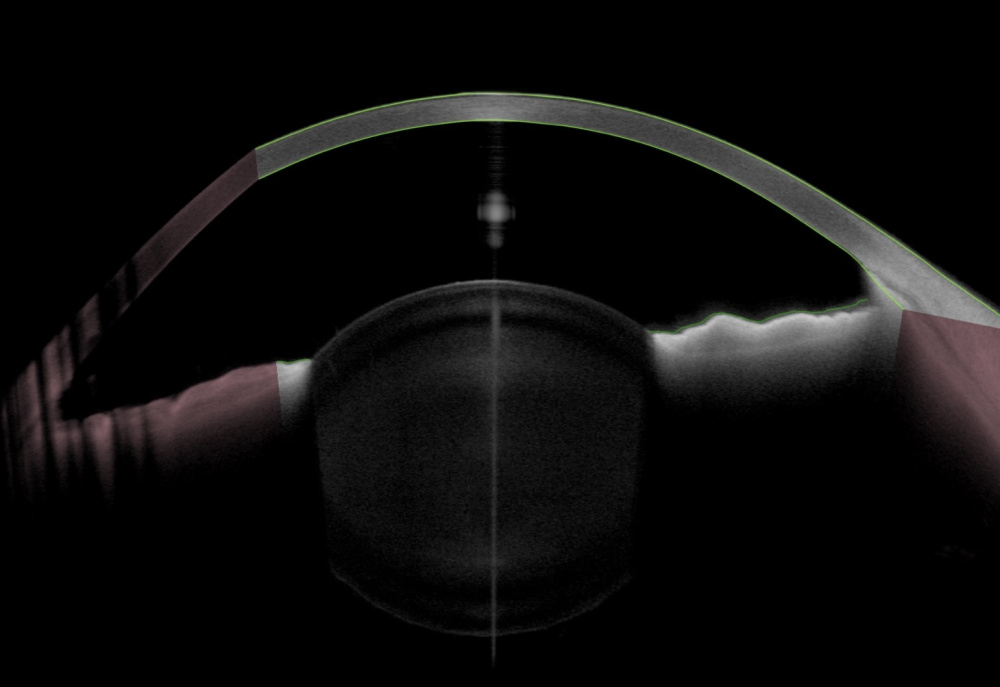

Título: Small Lens, Big Trouble

Autor: João Pedro Antunes

Coautores: Miguel Neves Lopes, Diogo Hipólito-Fernandes, Eduardo Silva, Pedro Gil

Instituição: ULS São José

Descrição: The anterior segment optical coherence tomography reveals a crystalline lens with a spheroidal shape, showing increased anterior and posterior convexity, reduced equatorial diameter, and increased anteroposterior thickness, consistent with microspherophakia.